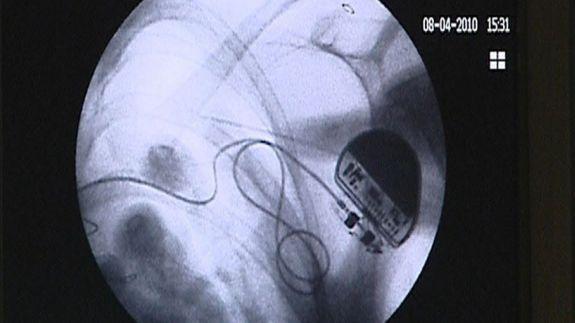

Las primeras pruebas han conseguido energía para mantener un marcapasos en funcionamiento

La investigación de seis meses de duración y que implicó pruebas en más de 32 voluntarios permitió descubrir que estos pequeños dispositivos son capaces de generar energía para hacer funcionar marcapasos y otros dispositivos similares que requieren de baterías voluminosas.

Los participantes que usaron el dispositivo durante una semana en el verano, el otoño y el invierno, mientras que va sobre sus rutinas diarias. Según los datos difundidos por los investigadores, la energía generada fue de promedio de 5-10 microwatios superior a la requerida por un marcapasos estándar.